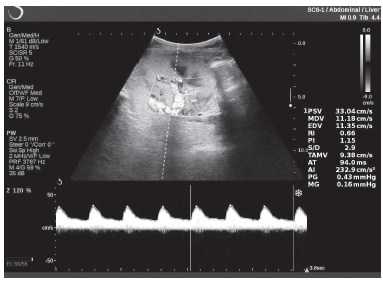

Клинический пример из первой группы. Пациент М., с хронической почечной недостаточностью. Трансплантация почки произведена от живого родственного донора. Трансплантат находится в правой подвздошной области. При нормальном функциональном состоянии трансплантата, показатели цветовой и спектральной допплерографии оценивались как удовлетворительные, с индексом резистентности не более 0,60 (рис. 1); показатели жесткости паренхимы почечного трансплантата при УЭСВ на различных участках составили от 20,05 до 29,18 кПа (рис. 2-4).

Рисунок 1. Ультразвуковое исследование в режиме цветовой и спектральной допплерографии в междольковых и сегментарных артериях у пациента М. Показатели кровотока в данном случае не изменены

Клинический пример из второй группы. Пациент К. перенес операцию пересадки почки от живого родственного донора. Трансплантат в левой подвздошной области. Индекс резистентности в междольковых артериях составил 0,70 (рис. 5). В сегментарных артериях индекс резистентности составил 0,66 (рис. 6). Показатели жесткости паренхимы почечного трансплантата при режиме УЭСВ составили от 31,6 до 36,9 кПа (рис. 7-9).

Рисунок 5. Исследование у пациента К. в режиме цветовой и спектральной допплерографии. Индекс резистентности в междольковых артериях почечного трансплантата составил 0,70